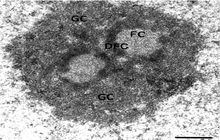

- Preparation of tissue sections for examination with a TEM microscope